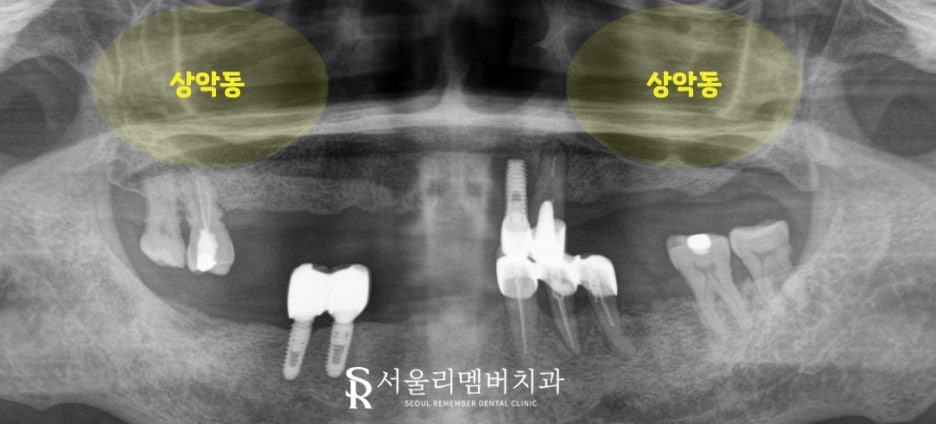

상악동과의 거리를 꼼꼼히 확인한 다음

환자에게 맞는 픽스처를 심어드렸습니다.

앞에서 언급했듯이 위쪽은 아래로 내려오는 힘이 전달되기에

아래쪽에 비해 제대로 된 고정력을 얻지 못할 확률이 큰데요.

따라서 좀 더 굵고 직경이 큰 픽스처를 사용하여

안정된 고정력을 얻을 수 있도록 유도했습니다.